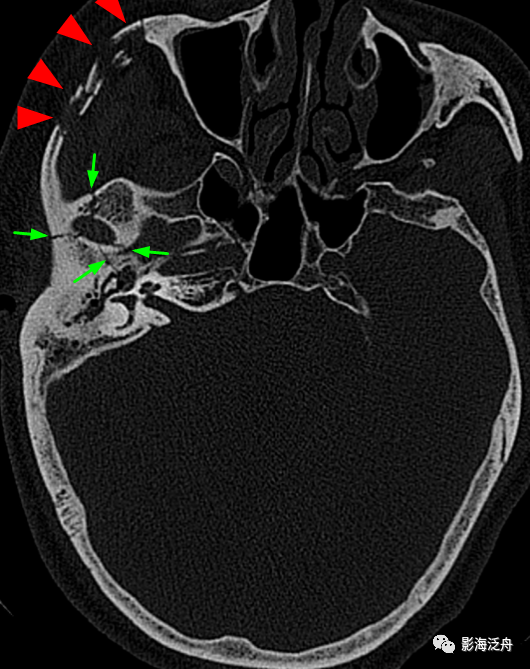

右侧颧弓骨折(红箭),注意对照前文的解剖标注图里的标注区2,颞骨与